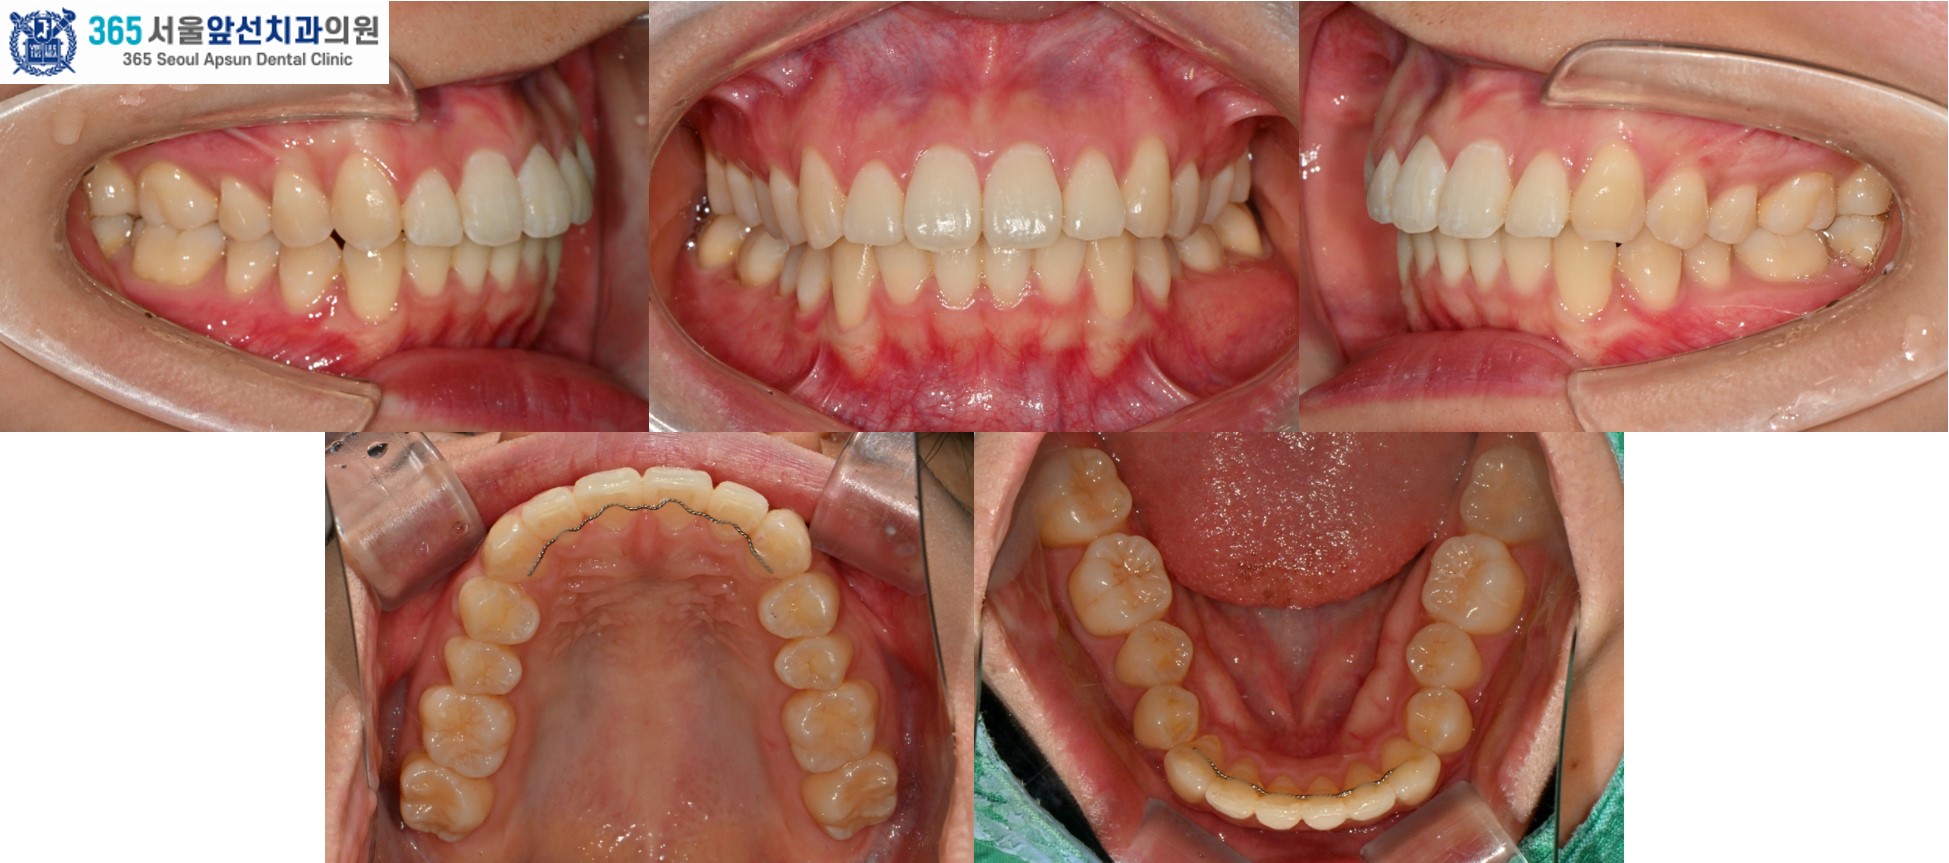

치료 후의 모습입니다. 아랫니 치열은 약 5개월, 윗니 치열은 약 7개월의 치료기간이 소요되었습니다. 앞니의 치열이 가지런하게 배열되어 환자분도 만족하셨습니다. 미소 시 자연스럽고 단정한 인상으로 변화하였습니다. 앞니 부분 교정 증례의 치료기간은 4-9개월 사이로 정도에 따라 상이합니다. 부분 교정 관심 있으신 환자분들께서는 365서울앞선치과로 내원하셔서 교정 진단 받아보시길 바랍니다. 감사합니다!

gif 촬영일자 2025.02.25. 2025.03.26. 2025.04.26. 2025.05.28. 2025.11.06. 2025.02.25. 2025.11.06. 2025.02.25. 2025.11.06. 2025.02.25. 2025.11.06. |